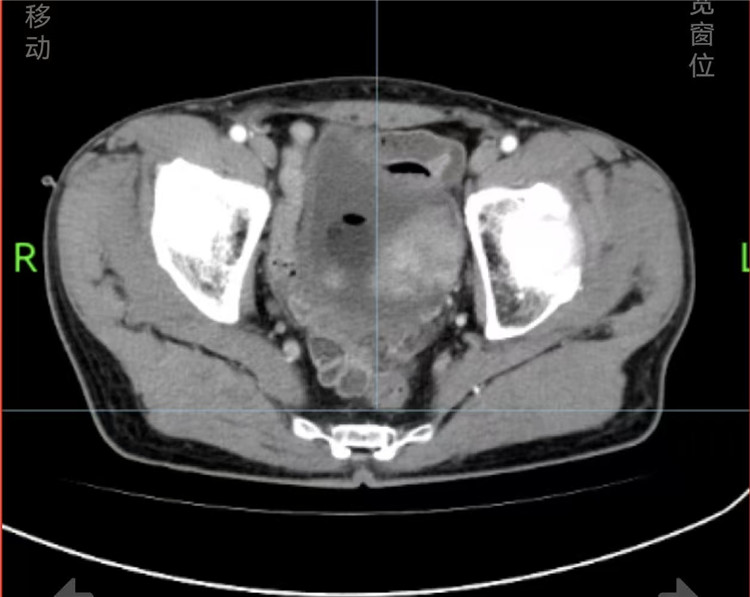

患者王嗲嗲(化名)三个月前因出现血尿,于某医院确诊为膀胱癌。为进一步治疗,王嗲嗲转至长沙泰和医院泌尿外科就诊。膀胱癌作为泌尿系统常见恶性肿瘤,常规治疗需行根治性膀胱切除术。然而,传统手术后患者需终身佩戴尿袋,严重影响生活质量。

为最大限度提升患者术后生活质量,长沙泰和医院泌尿外科团队迅速启动多学科协作(MDT)会诊机制,经充分评估与讨论,最终确定实施“膀胱根治性切除+原位回肠新膀胱术”这一高难度术式。该手术通过截取患者自身部分回肠,手工缝制成球状新膀胱,并置于原膀胱位置,以重建泌尿功能,使患者能够实现经尿道自主排尿,避免长期携带尿袋的不便。

在湖南省肿瘤医院泌尿外科蒋书算教授的现场指导与长沙泰和医院泌尿外科李琦主任团队的精细操作下,手术顺利完成。术中,团队完整切除了患者病变膀胱,并成功利用回肠组织构建新膀胱及尿流通道。术后患者恢复良好,目前已拔除尿管,实现自主排尿。